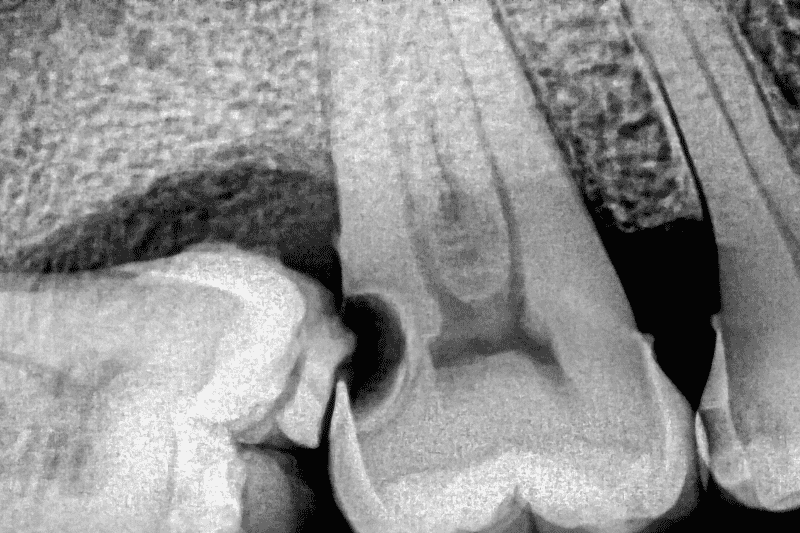

Dental X-ray showing infection at the root of a tooth, a common cause of tooth infection symptoms in Wetherill Park.

A tooth infection becomes serious when symptoms intensify or begin to interfere with normal daily activities. For example, increasing pain or visible swelling may indicate that the infection is spreading.